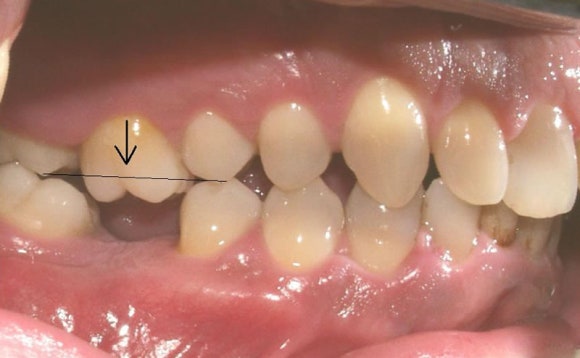

적절한 시기에 수복되지 않아서 교합이 틀어짐.

반대편 치아의 정출, 뒤 치아의 쓰러짐

뒤 치아가 쓰러지고, 치아가 빠진 부위 뼈가 퇴화함.

60대 남성의 임플란트, 상악동 수술, 뼈이식을 한 사례입니다.

사진에서 보듯 발치 한 부위를 비워둔지가 오래 되어서

해당부위 뼈의 양이 부족하고, 반대편 치아가 정출 되었으며, 뒤 치아가 쓰러져 있음을 알 수 있습니다.